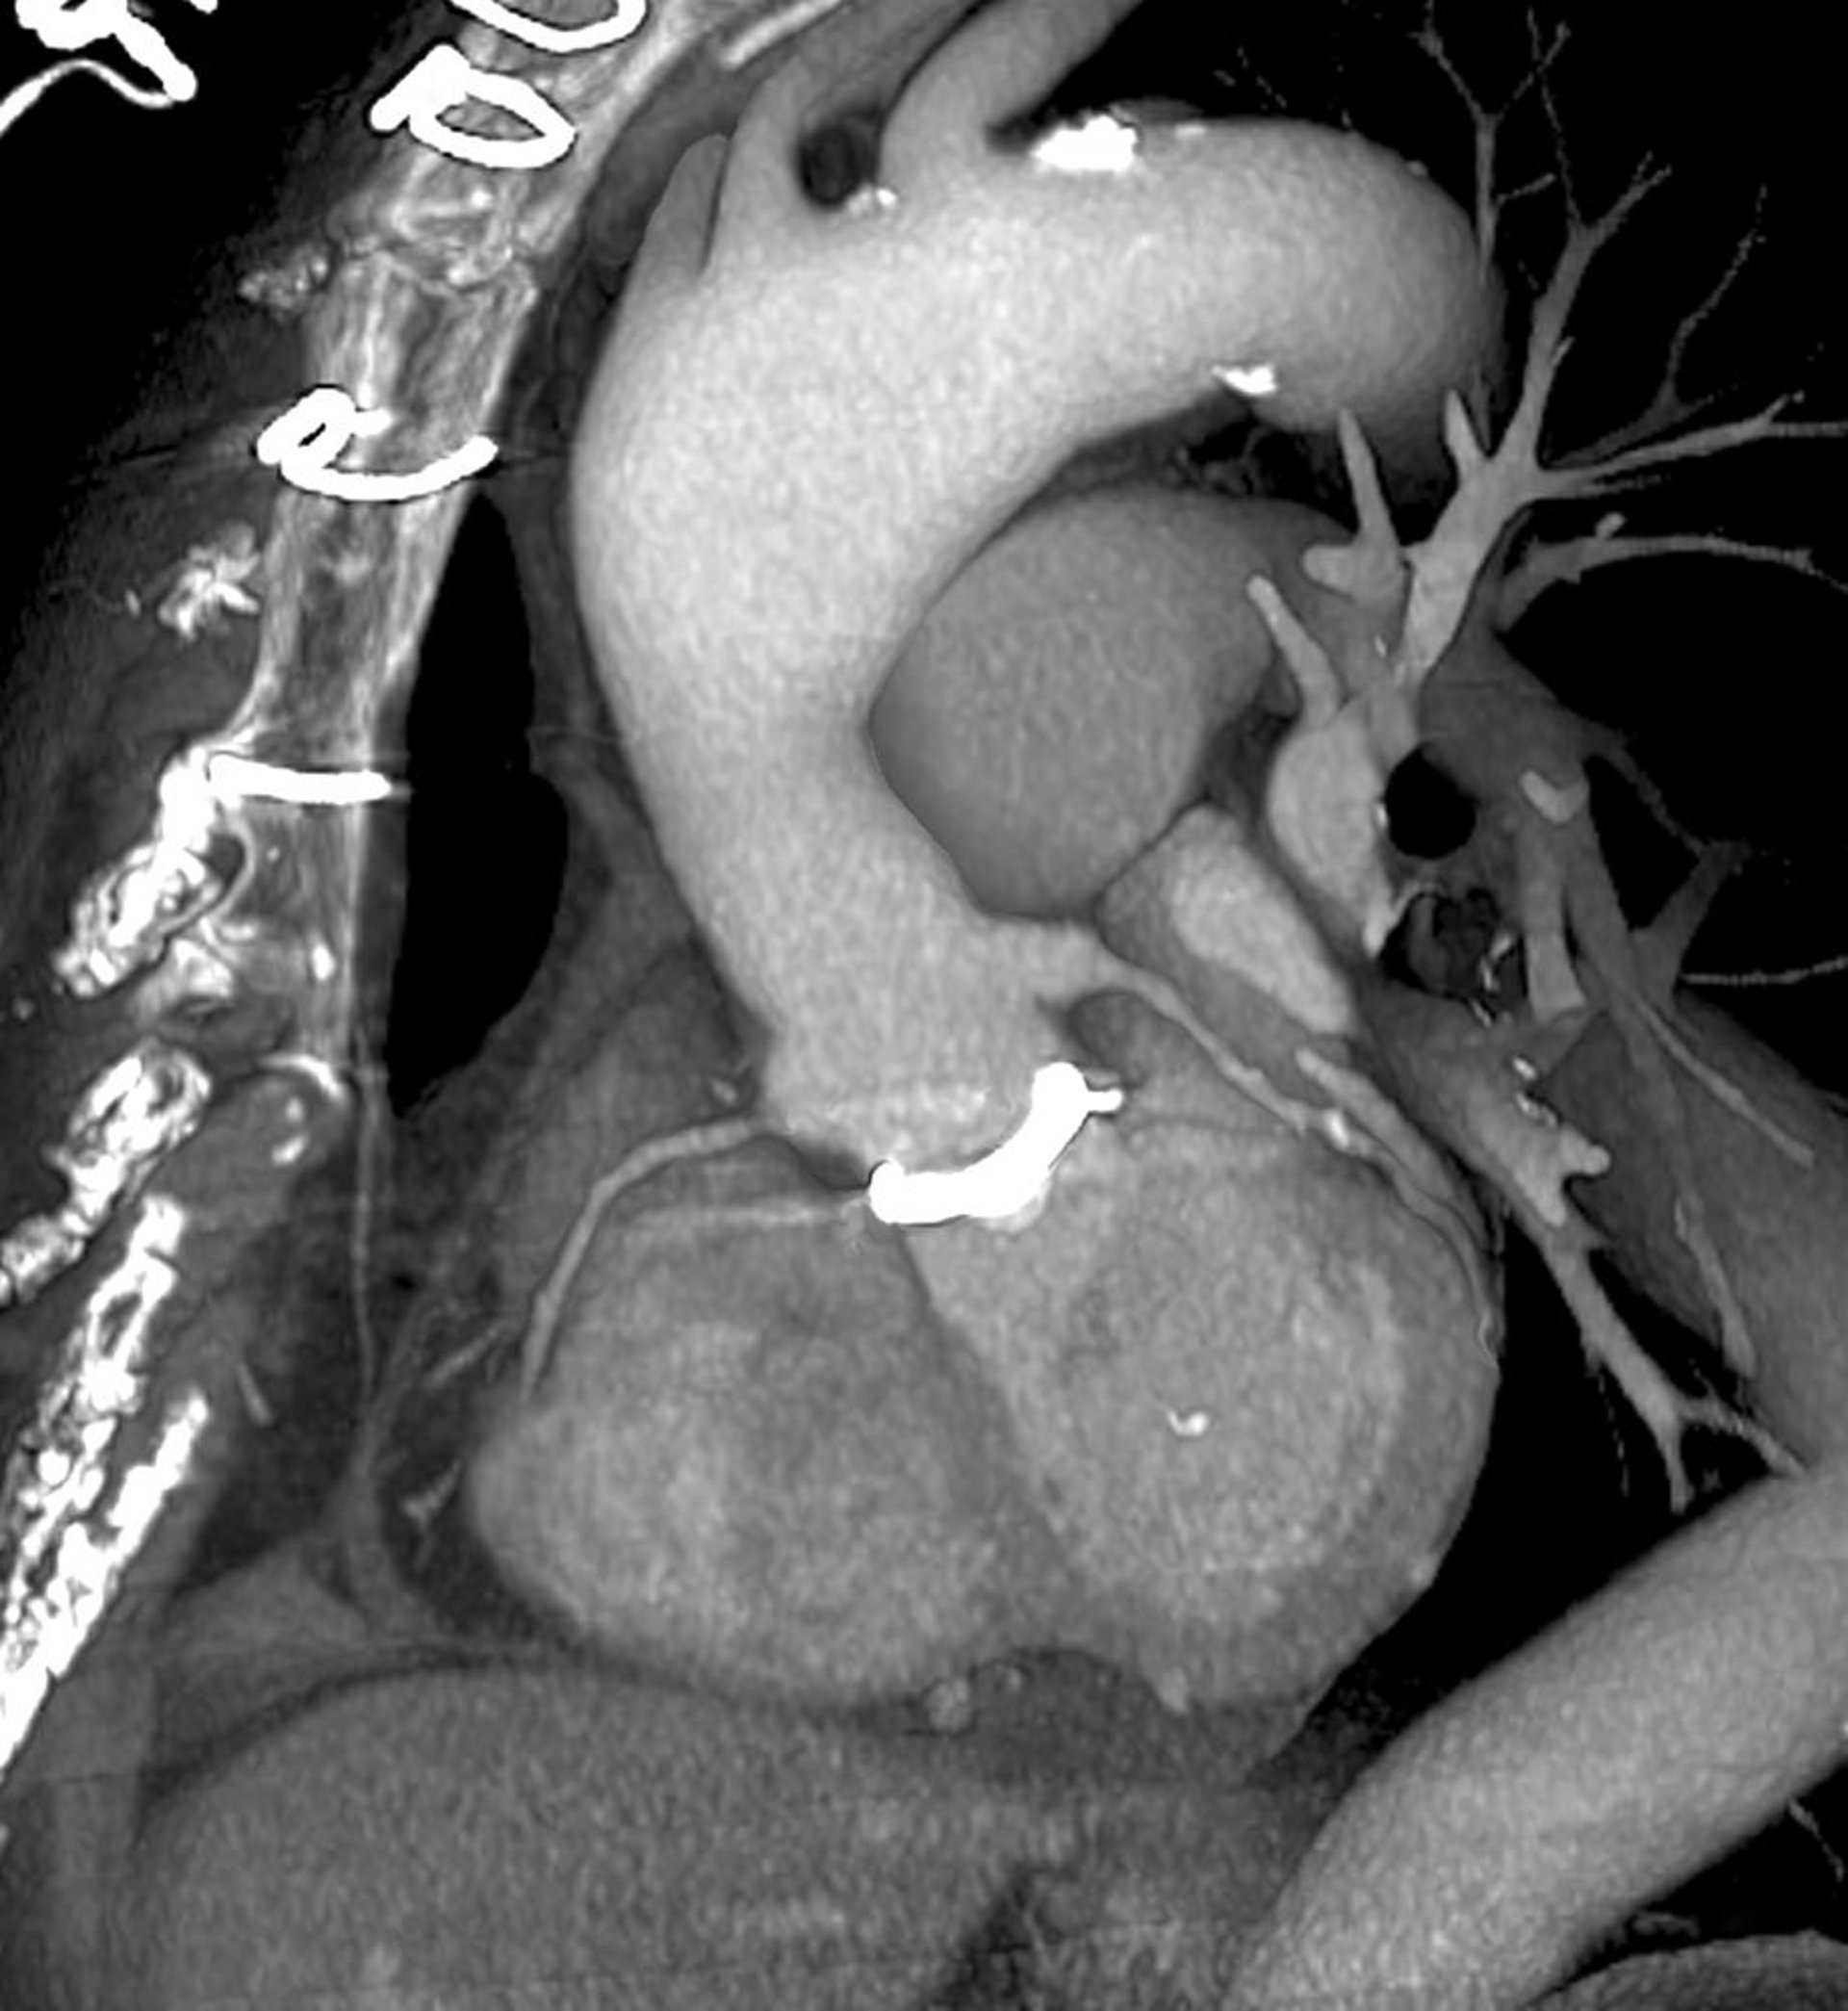

TC cardíaca (exploración 3D de la válvula cardíaca protésica)

Esta es una vista oblicua del lado izquierdo, mirando hacia la parte frontal del tórax (izquierda). La válvula cardíaca protésica (blanca) es visible en el centro, donde la aorta (parte central superior) se encuentra con el corazón (parte central inferior). Los puntos utilizados para cerrar el tórax son visibles en la parte superior izquierda.